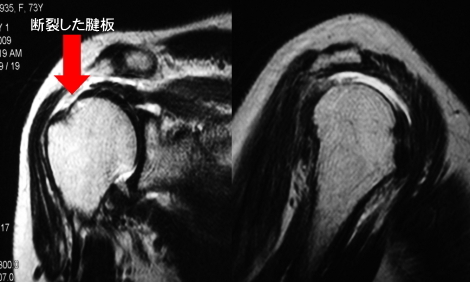

断裂していない腱板を関節鏡で滑液包側からみると

断裂した腱板を関節鏡でみると